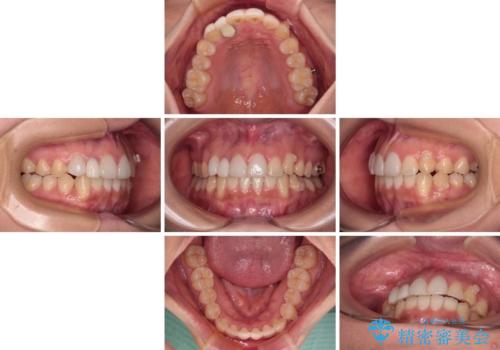

- 1年8ヶ月

- 5-10回